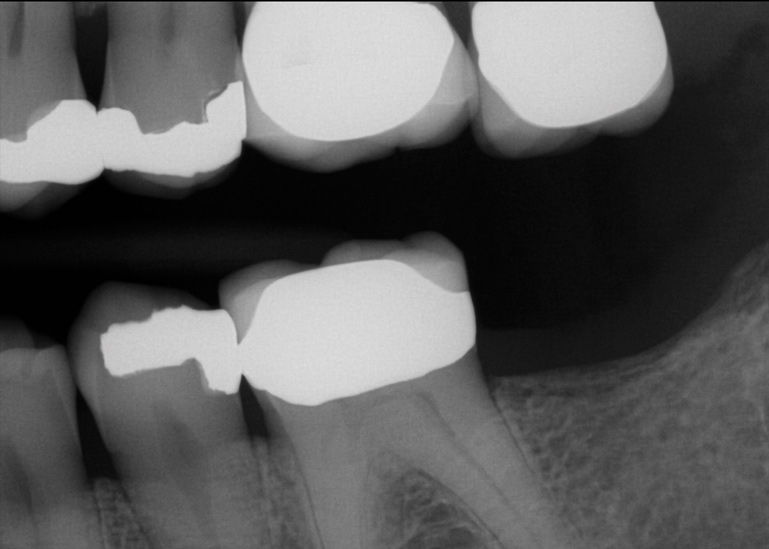

Fig 5. Patient No. 2 had an extraction of tooth No. 31 in 2009. Six years later, as shown, tooth No. 2 was extruded and needed to be removed due to caries.

Figure 5